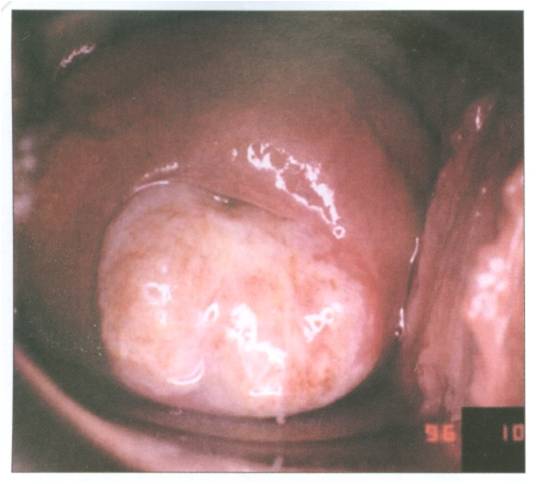

Kanker serviks adalah kanker yang menyerang leher rahim.Kanker yaitu tumor ganas yang terjadi di serviks. Kanker serviks berkembang ketika sel yang abnormal dalam serviks mulai membelah diri tanpa terkendali. Kemudian sel yang abnormal pada serviks berkumpul dan lambat laun menjadi tumor. Tumor terbagi dua yaitu tumor ganas dan tumor jinak. ( sumber : Faizah SA, Waspada Kanker Serviks )

Kanker serviks berawal dari lesi prakanker yang dalam waktu 5 - 15 tahun dapat menjadi kanker serviks invasif. Baberapa faktor resiko yang diduga turut berperan :